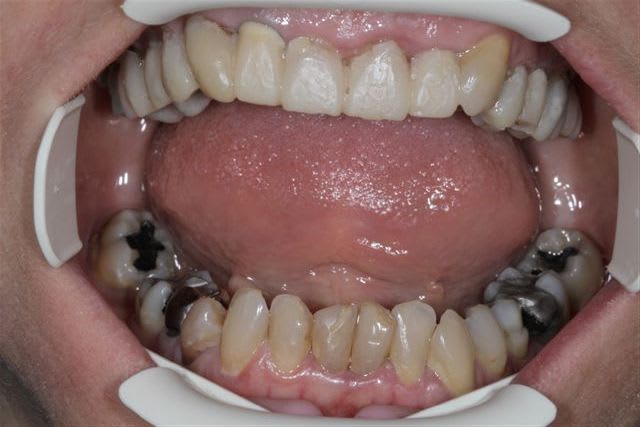

N'hésitiez pas çà me donner votre avis, patiente 47 ans ne supporte plus ses antérieurs, maquillées à la résine il y a quelques années.

Pas de demande concernant l'occlusion, ni les postérieurs, à fait des économies et veux s'offrir "un sourire", sur fond propre budget envisageable au départ 4000€

C'est un cas de réhab global, ortho et 28 couronnes.

Les secteurs post sont en mauvais état, l'occlusion est moche, et si tu ne fais que le sourire, tu auras de drôle de résultat et des casses de céram ou bien des antagonistes.

Vu les axes actuels des antérieures, soit tu gardes la même forme et les mêmes axes et tu auras de dents assorties mais pas vriament plus esthétiques. Sinon c'est ortho et la totale. Si tu changes la forme sans amélioration de l'esthétique ce sera l'echec mécanique assuré.

Je suis assez d'accord avec Ceramik, ce qui me saute aux yeux,outre l'esthétique bien sur, ce sont les courbes occlusales de la patiente, notamment secteur 2 et 3 en postérieurs(26 ne semble pas en occlusion, et 27 sur une pointe).

Le secteur antérieur doit donc supporter pas mal de contraintes... d'autant plus que le guide incisif semble assez fermé.

Perso, je ne toucherai à rien en antérieur,( d'autant plus avec du tout céram) tant que les courbes postérieures ne sont pas rétablies.